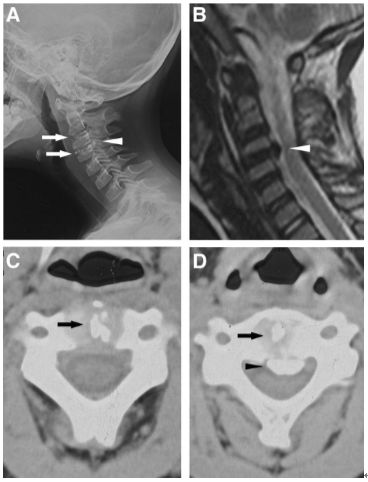

齿状突加冠综合征(Crowned dens syndrome)是指患者以急性颈痛伴随颈椎活动受限就诊,常伴发热,且影像学上表现为齿状突上方或周围出现大小不一、高密度、不规则的钙沉积影,但主要发生在齿状突后侧。因影像学征象犹如齿突戴上了一顶皇冠(如下图),因而得名齿状突加冠综合征,是因钙盐晶体在枢椎齿突周围软组织中沉积形成的。早在1985年,Bouvet等 (Arthritis Rheum, 1985) 首先报道此病。

颈椎CT冠状位重建显示犹如齿突戴上了一顶皇冠故得名齿状突加冠综合征

一位88岁女性患者,主诉急性颈痛伴发热2个月入院。体温波动在38-39.3℃,无视力模糊,无神经及脊髓压迫征象。颈椎CT+矢状位重建显示寰椎横韧带的曲线状钙化(图A,箭头所示),线性钙化(图B,箭头所示),以及齿状突周围的冠状钙沉积(图C,箭头所示)。给予短期非甾体抗炎药和泼尼松龙(15mg/d)后,其上述症状完全缓解。同时,作者指出这类疾病通常不需要长期用药。

【病例2】2014年Kuriyama等发表在加拿大医学杂志(CMAJ)的病例。

一位84岁的男性患者,因“急性颈痛、僵硬伴发热”就诊。查体:颈椎向各个方向活动受限,无明显神经病变体征。实验室检查:血沉及C反应蛋白偏高。颈椎CT平扫提示齿状突横韧带钙化(箭头所示),从而诊断为齿状突加冠综合征。给予洛索洛芬治疗一周后,上述症状完全缓解,而且炎性指标恢复正常。

【病例3】2018年李永超等发表在中华医学杂志的病例。

患者女,76岁。无明显诱因下出现颈部疼痛、僵硬伴发热 3 d 入院 ,颈部疼痛呈间歇性,颈痛视觉模拟评分(VAS)为7分,体温37.7~38.8℃,无四肢疼痛麻木,无行走不稳,二便正常。既往无痛风、类风湿关节炎病史。入院体检:颈椎旋转明显受限,颈部肌肉僵硬,未查及明显神经或脊髓损伤体征。实验室检查:白细胞11.2×109/L,红细胞沉降率35.4 mm/h,超敏C反应蛋白14.7 mg/L,类风湿因子及降钙素原正常。颈椎CT平扫示齿状突后侧寰椎横韧带弧形钙化(左图箭头)和竖直线样钙化(右图箭头)。依据患者病史、体征及辅助检查,齿状突加冠综合征可基本诊断。入院后给予氯诺昔康 8 mg静脉滴注每日2次,地塞米松起始量10 mg静脉滴注每日1次,3日后改为5mg/d。连续治疗5 d后,患者入院时症状明显缓解,复查白细胞、红细胞沉降率、超敏C反应蛋白均恢复正常。随访半年,未有颈痛伴发热症状出现。